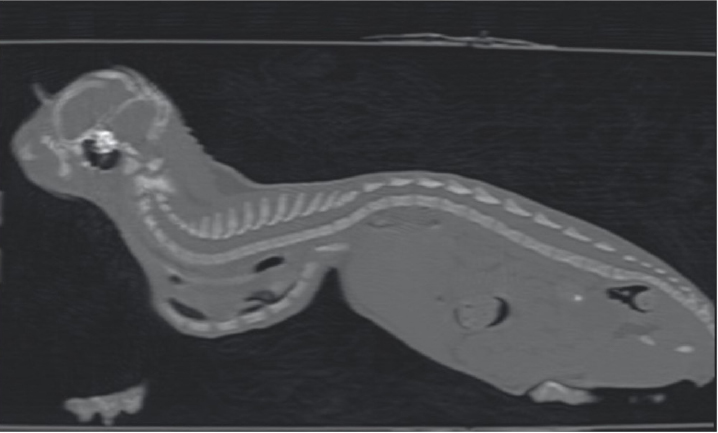

Fig. 3. Longitudinal reconstruction from CT scan. Notice the close relationship between the xiphoid process and the ventral aspect of the vertebral column.

One month later, the kitten weighted 550 g and presented again for intermittent tachypnea, needing oxygen administration, and exercise intolerance. A preoperative CT was performed to evaluate the exact position of the intrathoracic structures and to assess safe corridors for the needle passage. CT was performed using a 20 slice TC scanner (Siemens® Somatom Sensation Open, Munich, Germany) with a 140 Kw and 150 mAs technique, in the awake patient, using a Plexiglas “mouse trap” (VetMouse trapTM) to restrain the animal. Only basal scans were obtained with 2 mm slice thickness, using 0.5 seconds rotation time. CT confirmed radiographic findings, adding more details (Fig. 3). Tomographic images revealed a complete dislocation of the heart into the left hemithorax, with complete atelectasis of the caudal portion of the cranial left lung lobe and partial atelectasis of the caudal left lobe near the hilum. The heart and the tracheal bifurcation were dislodged cranially compared to the normal anatomical position. The aortic arch was completely left-placed, together with the heart, but properly positioned at the level of the aortic hiatus. The caudal vena cava was dislocated to the left, resulting in a more central position, exactly interposed between the 12th vertebral body and the xiphoidal cartilage apex. The caudal vena cava and the aorta completely occupied the narrowed diaphragmatic portion of the thorax at the level of the xiphoid cartilage.

The cat in this report was 3 months old and, based on the pectus severity index, had a severe pectus excavatum; therefore, an external splinting technique with a 3D-printed cast, customized on the base of CT images was chosen. CT scan was useful to better assess skeletal deformities, anomaly of the intrathoracic structures, and safe corridors for the needle passage. Moreover, CT was fundamental to design the splint. Five sutures were applied, the most caudal three being gradually pulled outward the concave part of the sternum and the other two directly ligated to the splint. The decision to surgically approach the seventh sternebra and xiphoid process to place the corresponding suture under direct vision was taken based on the result of the CT scan. CT images showed a close relationship between the seventh sternebra and the xiphoid process (Fig. 7), with the aorta and caudal vena cava occupying most of the thoracic space, making blind passage of the needle too risky. With this approach, the skeletal segment could be grasped and pulled ventrally, increasing the space for a secure passage of the needle. There were no surgical complications such as organ laceration or puncture, nor postoperative complications such as re-expansion pulmonary edema. The concern of the development of the re-expansion pulmonary edema, based on the sudden increase of the intrathoracic pressure due to the correction of the sternal concave deformity, lead the authors to the decision to gradually correct the sternal deformity. In this way, the increase in intrathoracic pressure and, therefore, lung re-expansion occurred little by little, reducing the risk for this complication. For these reasons, the sutures were gradually tightened during the first 2 weeks in response to the skeletal development of the kitten, and then kept in place for further 2 weeks to allow consolidation. The use of an electrician terminal block applied to the ventral part of the splint between the two rows of holes for the passage of the sutures perfectly fit this purpose. These locking clips allowed holding the sutures in position without the need to untie them each week.